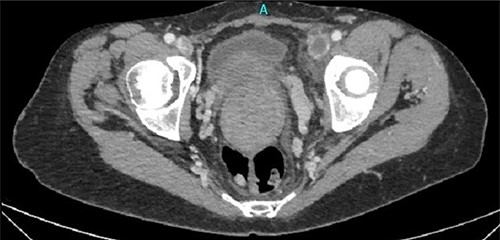

One month later, after vascular consultation, a chest and pelvis computed tomography angiography was performed and a huge mass originating from the uterine wall was revealed (26 cm in diameter) (Fig. 1). The mass compressed the surrounding organs, especially IVC (Fig. 2). Furthermore, thrombosis of left femoral and external and common iliac veins, as well as infrarenal IVC patency (without clarification of IVC thrombosis), was detected. The common, internal and external right iliac veins were patent, and no PE was detected.

Thrombosis of left femoral and external and common iliac veins.